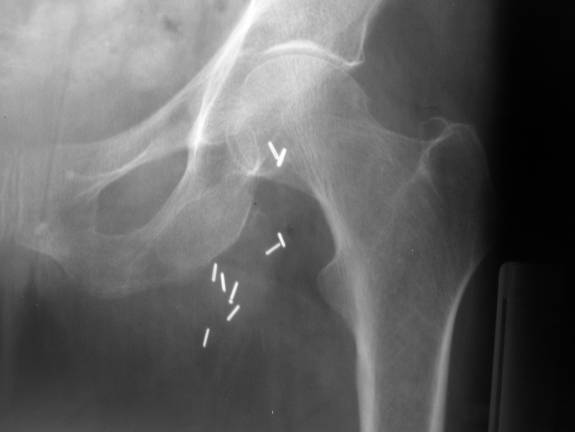

Hip pain after a fall